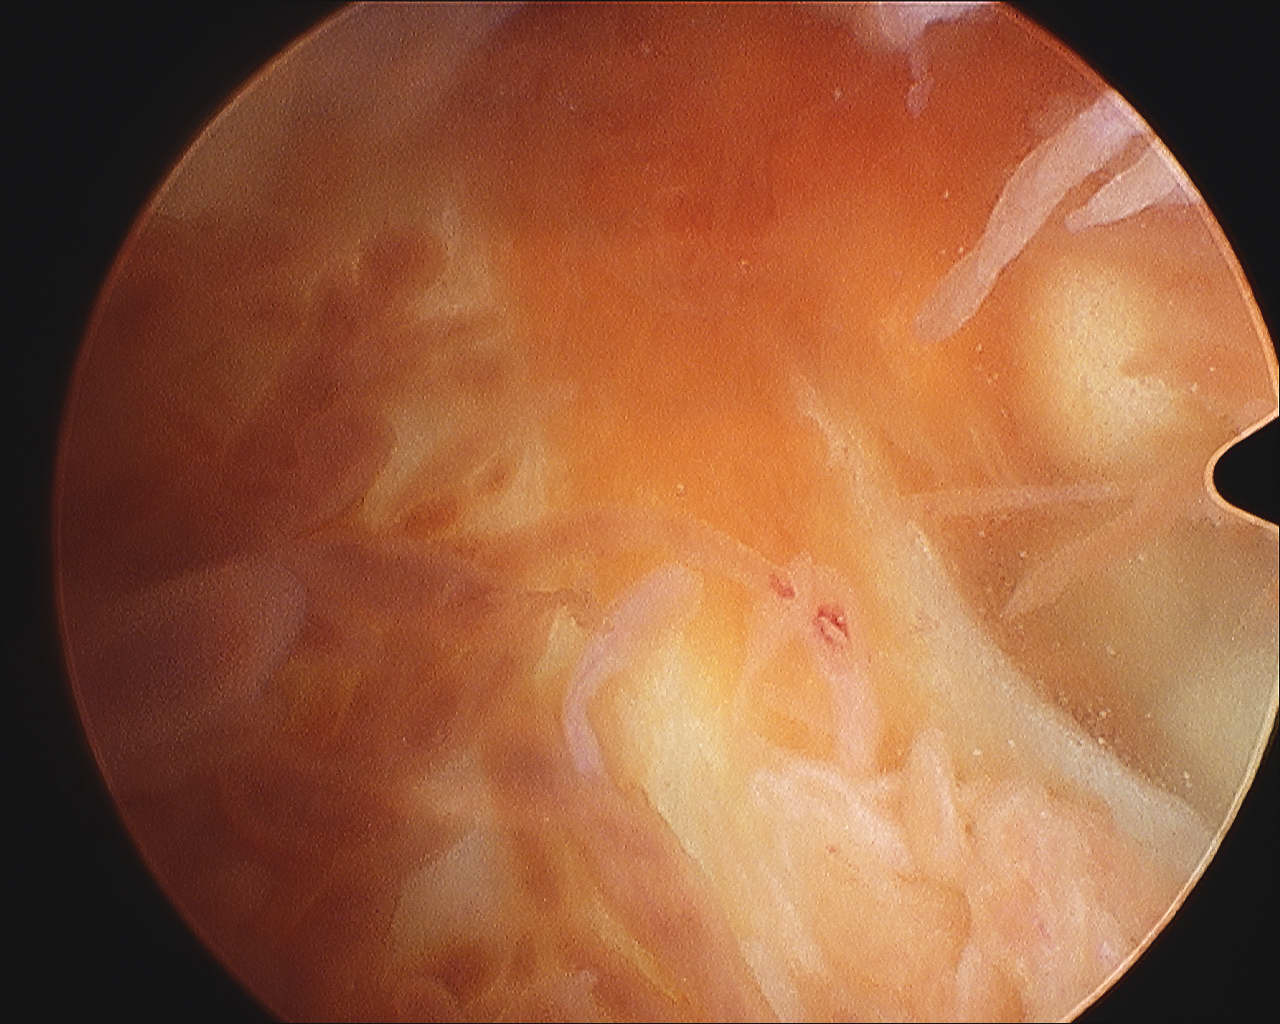

Localized / nodular PVNS anterior knee joint

Localized / nodular PVNS posteromedial compartment knee

Diffuse knee joint